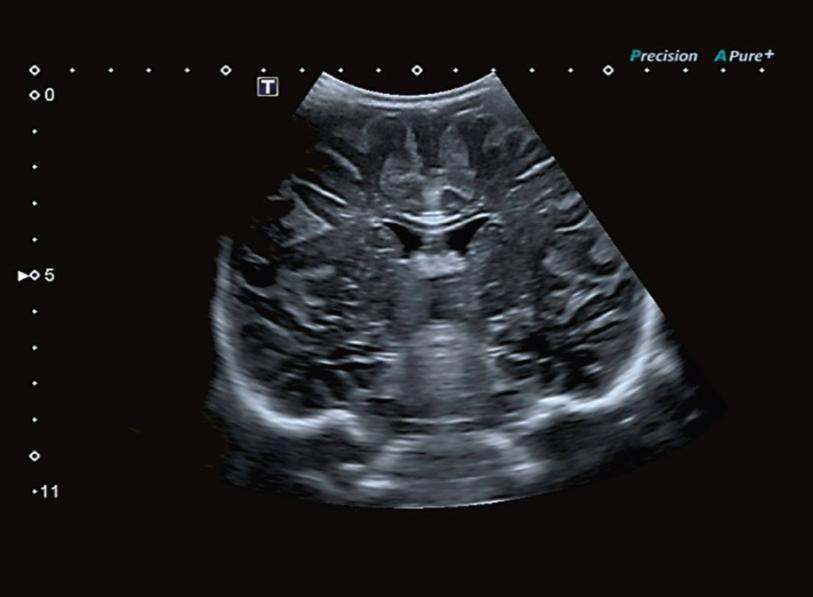

Precision Imaging (Прецизионная визуализация) ультразвуковой системы Aplio позволяют получать более реалистичные изображения и обеспечивает высокую степень послойной дифференцировки тканевых структур и анатомическую точность в визуализации деталей.

Режим дифференцированной тканевой гармоники (DTH) обеспечивает высокую детализацию глубоко расположенных структур. Поскольку в этом режиме за один импульс передаются сигналы на двух различных частотах, изображения обладают непревзойденным пространственным разрешением и контрастностью, а также большей глубиной проникновения.